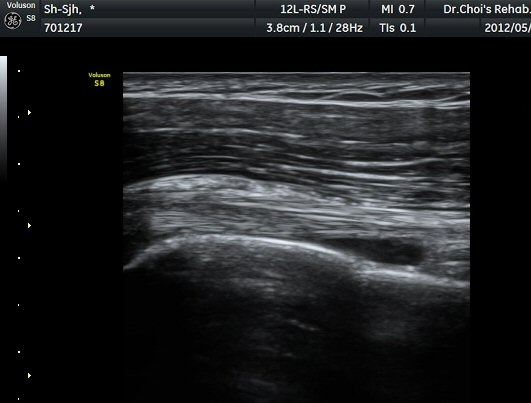

ÃÊÀ½ÆÄ °Ë»ç

Á߸³»óÅ ¾î±ú ¾Õ Ⱦ´Ü¸é°Ë»ç¿¡¼­ À̺ειڱ٠ÁÖÀ§¿¡ ¼ö¾×Àú·ù°¡ °üÂûµÇ°í(»çÁø 1) ÆÄ¿öµµÇ÷¯

°Ë»ç¿¡¼­ Ç÷·ùÁõ°¡°¡ °üÂûµÈ´Ù(»çÁø 2). À̵ιڱ٠Á¾´Ü¸é°Ë»ç¿¡¼­µµ °Ç ÁÖÀ§ ¼ö¾×Àú·ù°¡ È®ÀÎ